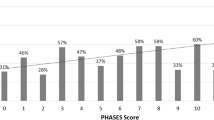

According to our classification system, 66.6% (64) of the aneurysm projections were located in the quadrant position, while 33.3% (32) were in the linear position. In the linear position, the anterior projection predominated with 17 aneurysms, followed by 9 with a superior projection, 4 with a posterior projection, and 2 with an inferior projection. In the quadrant position, the anterosuperior projection was the most prevalent, with 34 cases, followed by 14 with an anteroinferior projection, 8 with a posterosuperior projection, 2 with a posteroinferior projection, and 6 cases displaying a complex projection. In our study, overall, the distribution of aneurysm projections was as follows: 35.4% were anterosuperior, 17.7% were anterior, 14.58% were anteroinferior, 9.37% were superior, 8.3% were posterosuperior, 6.25% were complex, 4.16% were posterior, 2.08% were posteroinferior, and 2.08% were inferior.

According to our own classification system, two-thirds of the aneurysm projections were in quadrant orientation and one-third in linear orientation. Anterior projection in linear position (53%) and anterosuperior projection in quadrant position (53%) were the most common projections. When linear and quadrant orientations were evaluated together, the most common projection was anterosuperior (35.4%), followed by anterior (17.7%) and anteroinferior (14.58%) projections. Superior was seen in 9.37%, posterosuperior in 8.33%, complex in 6.25%, and posterior in 4.16%. The least common projections were inferior and posteroinferior projections with 2.08% (Table 3).